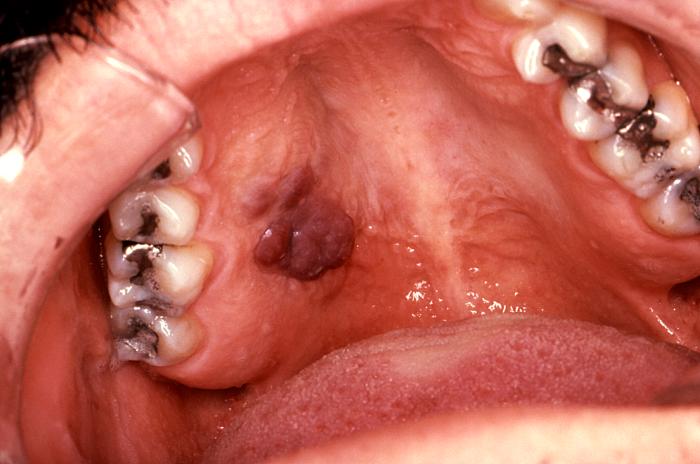

Sarcoma de Kaposi en paladar duro

El sarcoma Kaposi es la neoplasia intraoral más común que se observa en el SIDA y generalmente se presenta en el paladar duro, encías y zona del trígono retromolar, como una mancha violácea o rojiza, de límite difuso, indolora, que en el 20% de los casos puede ser la primera manifestación.

Esta neoplasia a veces presenta un aspecto tumoral, pero muchas veces se observa como una mácula rojiza, en el primer caso tiene un peor pronóstico.

Este tumor es multifocal y en la boca puede observarse varias lesiones en paladar y/o encía, aunque lo más frecuente es que el paciente tenga otras lesiones  en piel de extremidades superiores, torax y cara.